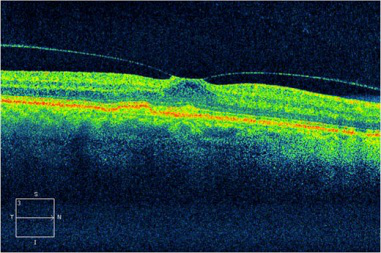

當(dāng)葡萄膜炎危害到黃斑地區(qū)或眼睛神經(jīng)時(shí),則很有可能會(huì)出現(xiàn)黃斑前膜、黃斑及眼睛神經(jīng)浮腫、球后視神經(jīng)炎、眼底黃斑下新生兒毛細(xì)血管等非常容易對(duì)眼睛視力非常容易失明的并發(fā)癥。

(OCT查驗(yàn)顯示信息雙眼的黃斑前膜,化學(xué)纖維膜在黃斑表層造成伸展的能量,可導(dǎo)致黃斑浮腫或孔裂,導(dǎo)致視線中間出現(xiàn)冷色)